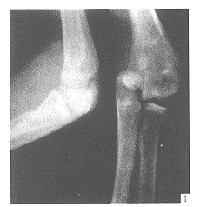

肘关节侧方脱位3例

Three cases of lateral dislocation of elbow